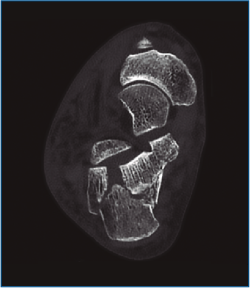

En las fracturas de calcáneo donde se afecta la articulación subastragalina posterior existe un trazo de fractura principal que separa 2 grandes fragmentos: el anteromedial “fijo” y el posterolateral, que se desplaza. Un segundo trazo de fractura ocasiona el hundimiento y la apertura de la subastragalina posterior. Sanders realizó una clasificación de estas lesiones intraarticulares basándose en la conminución y en las imágenes de tomografía computarizada (TC)(1).

Primero, realizamos limpieza de tejidos blandos y localizamos el flexor hallucis longus (FHL), que será el límite medial de seguridad. Recordamos que, en las fracturas de grado II de Sanders (Figuras 1 y 2), permanece íntegro un gran fragmento anteromedial, mientras que el fragmento posterolateral se desplaza. Tras la limpieza, identificamos la fractura (Figura 3) y movilizamos el fragmento lateral. Luego cambiamos los portales e introducimos el artroscopio por el portal medial, que nos permite acceder hasta el seno del tarso y visualizar el ligamento interóseo talocalcáneo. A través de un pequeño abordaje en la cara lateral del calcáneo reducimos la articulación subastragalina posterior (Figura 4A).

Figura 1. Fractura del calcáneo Sanders IIA.

Figura 2. Fractura del calcáneo Sanders IIB.